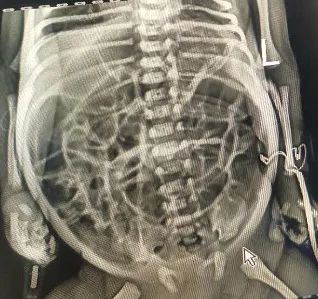

近日,在國家兒童醫學中心(上海)、上海交通大學醫學院附屬上海兒童醫學中心外科專家團隊的幫助下,南疆地區首例腸神經發育不良早產兒腹腔探查及回盲部T型造瘻術成功開展。

患兒孕周32周+2天,出生體重僅為1.69kg,腹脹導致患兒無法經口餵養,需長期靜脈營養,且腸腔擴張使得敗血症難以控制。隨着患兒腹脹症狀日益加重,隨時可能出現腸道穿孔、壞死,但喀什地區新生兒外科領域的醫療技術水平暫時無法支持手術治療。

上海專家組與喀什地區第二人民醫院新生兒科、普外科、麻醉科、手術室通力合作制定了詳細的診療計劃,對術前、術中和術後的治療進行了周密的安排,多科室分工協作,手術期間,克服了年齡小、體重低、病情複雜等諸多困難,利用微創技術完成了回盲部T型造瘻術,徹底解決了患兒腸管充氣擴張,結腸無活力的症狀,取得手術成功。近日在喀什二院新生兒監護室團隊的精心呵護下,患兒感染及腹部症狀日益好轉,通過造瘻口的護理和餵養知識的培訓後,患兒已在父母的陪同下順利出院。